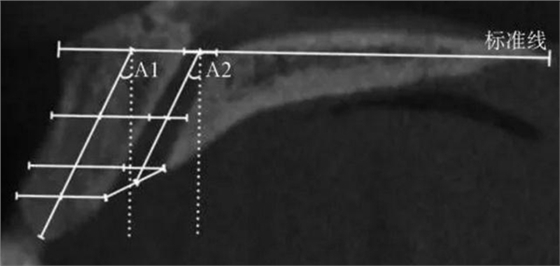

(1)正中矢狀面(圖1~3)。所使用的測量參數(shù)及其定義如下所述。鼻腭管高位直徑(S1):標準線交鼻腭管處的管徑;鼻腭管中位直徑(S2):鼻腭管長軸中點處的管徑;鼻腭管低位直徑(S3):管后壁腭側骨最低點至對應管前壁的水平管徑;切牙孔開口直徑(S4):管后壁腭側骨最低點至唇側骨低位厚度和管前壁交點的直線距離。唇側骨高位厚度(T1):S2平面處唇側骨板水平厚度;唇側骨中位厚度(T2):S3平面處唇側骨板水平厚度;唇側骨低位厚度(T3):唇側骨最凸處骨板水平厚度。鼻腭管長度(L1):S1與S4中點間的距離;唇側骨長度(L2):唇側骨下端最低點經(jīng)T1、T3中點至標準線的直線長度。鼻腭管傾斜角度(A1):L1和標準線的垂線所成角度;唇側骨傾斜角度(A2):L2和標準線的垂線所成角度。

A1:鼻腭管傾斜角度;

A2:唇側骨傾斜角度。

圖 3 矢狀面鼻腭管傾斜角度測量方法

Fig 3 Measurements ofinclination angle of the nasopalatine canal